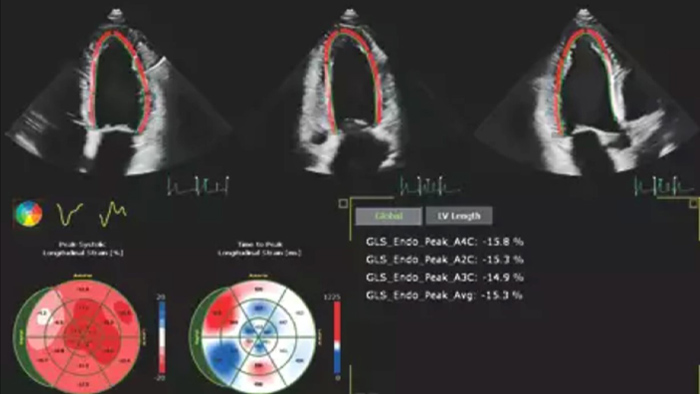

La ecocardiografía suele ser la primera prueba de imágenes cardiacas que se realiza en pacientes con sospecha de insuficiencia cardiaca. Un ecocardiograma nos proporciona una gran cantidad de información sobre la estructura y la función cardiaca utilizando tanto las herramientas 2D como las 3D. En muchas situaciones, la ecocardiografía puede ayudarnos a comprender la etiología de la insuficiencia cardiaca. Uso rutinariamente la información derivada tanto del análisis como de la deformación 2D y 3D para entender mejor a mis pacientes. AutoStrain, Dynamic HeartModel y Auto RV son herramientas valiosas que se utilizan tanto en el diagnóstico como en el control de pacientes con insuficiencia cardiaca.”

Las herramientas de adquisición de imágenes sólidas y reproducibles son importantes para diagnosticar y controlar la progresión de la enfermedad en la insuficiencia cardiaca. Las directrices actuales apoyan el uso de herramientas avanzadas de ecocardiografía, como la evaluación 3D y la deformación longitudinal de los volúmenes y funciones del VI y el VD.

Automatización para una cuantificación cardiaca reproducible sólida y probada tanto en 2D como en 3D.

Cuantificación mediante Dynamic HeartModel.